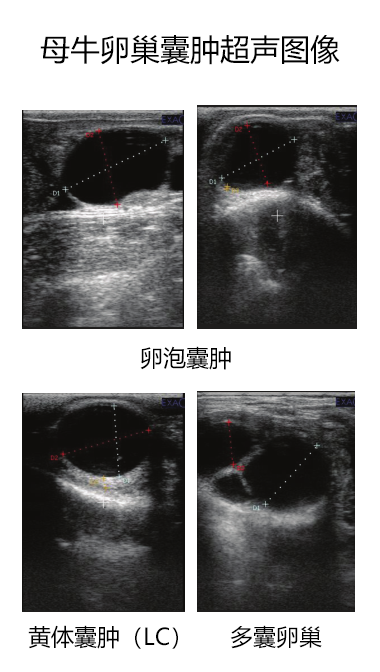

牛用B超机检测母牛卵巢囊肿的超声图像

兽用B超机对母牛卵巢囊肿的超声检测

母牛存在两种类型的卵巢囊肿:滤泡囊肿由未黄体化的薄壁形成,而黄体囊肿显示黄体化迹象并包含厚壁,可以认为是滤泡囊肿的高级形式。在实践中,由于存在中间形式,囊肿性质的诊断变得复杂。 这种区别很重要,因为治疗会因诊断出的卵巢囊肿类型而异。

在黄体囊肿( LC)中更常观察到直径 > 5 mm 的卵泡,这是鉴别诊断的补充标志。使用这些标准,大约 85% 的病例可以做出正确诊断。因此,牛用B超机在诊断卵巢类型方面比手动触诊更准确,因为它能够检测黄体结构。

母牛卵巢囊肿的超声图像